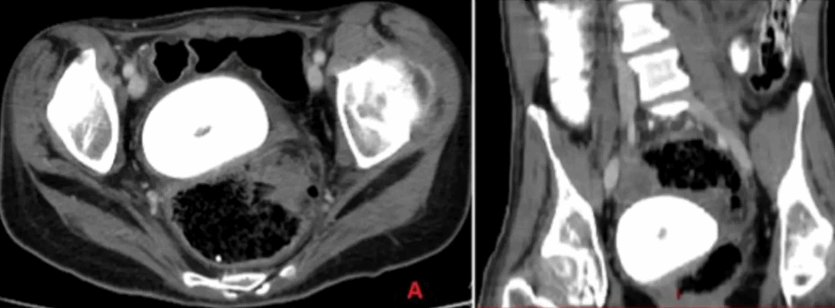

عثر أطباء في لبنان على حجر مهبلي نادر للغاية – بحجم برتقالة – موجود في حوض امرأة.

دراسة حالة حديثة نشرت في مجلة

Urology Case Reports

تناولت بالتفصيل الاكتشاف الاستثنائي - في هذه الحالة، لدى امرأة طريحة الفراش تبلغ من العمر 27 عامًا مصابة بالشلل الدماغي.

وكشف التصوير المقطعي للحوض والبطن عن السبب.

وتتشكل حصوات المهبل "عن طريق ترسب الأملاح غير العضوية عن طريق البول الراكد داخل المهبل"، وفقًا لورقة بحثية نُشرت عام 2019 في مجلة الطب. وقال الباحثون إنه بسبب ندرة هذه الحالة، فقد تم تشخيصها بشكل خاطئ في كثير من الأحيان في الماضي.

وكان التكوين كبيرًا جدًا لدرجة أنه كان يضغط على مثانة المرأة، مما أدى إلى المزيد من تسرب البول.

وقام أطباء من الجامعة اللبنانية في بيروت بفك التشكيل باستخدام العلاج بالليزر عبر الموجات فوق الصوتية من جهاز تم وضعه على بطن المرأة.

ثم استخدم الأطباء الملقط لإزالة الشظايا في إجراء مدته ثلاث ساعات.